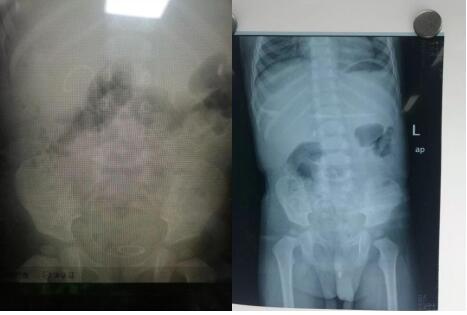

21点游戏攻略站 泌尿外科成功为一岁半患儿实施 尿道结石钬激光碎石术